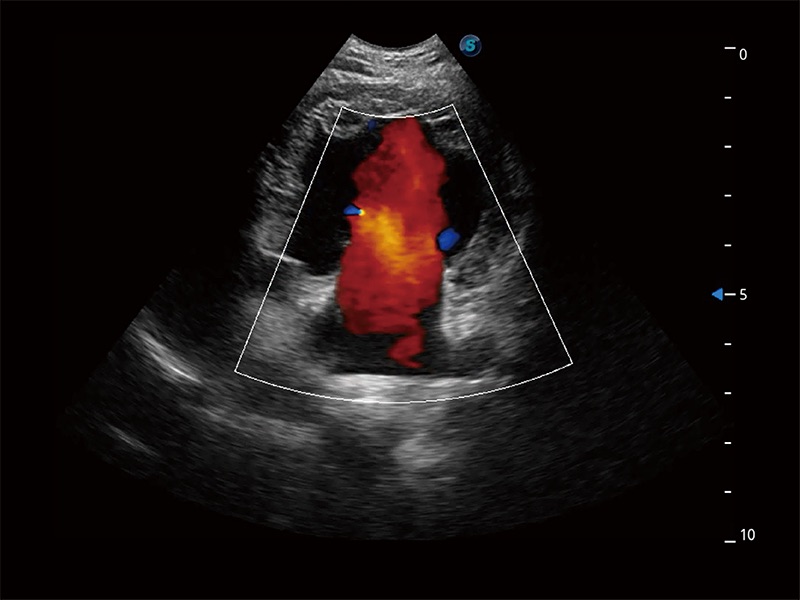

• Bright Flow 立體血流成像

在傳統(tǒng)二維血流成像的基礎(chǔ)上,呈現(xiàn)血流的立體感,具有動感的生命力之美。即便是微小的血管也能輕松應(yīng)對,提高了血流的視覺敏感性。

(犬)胎兒主動脈弓立體血流